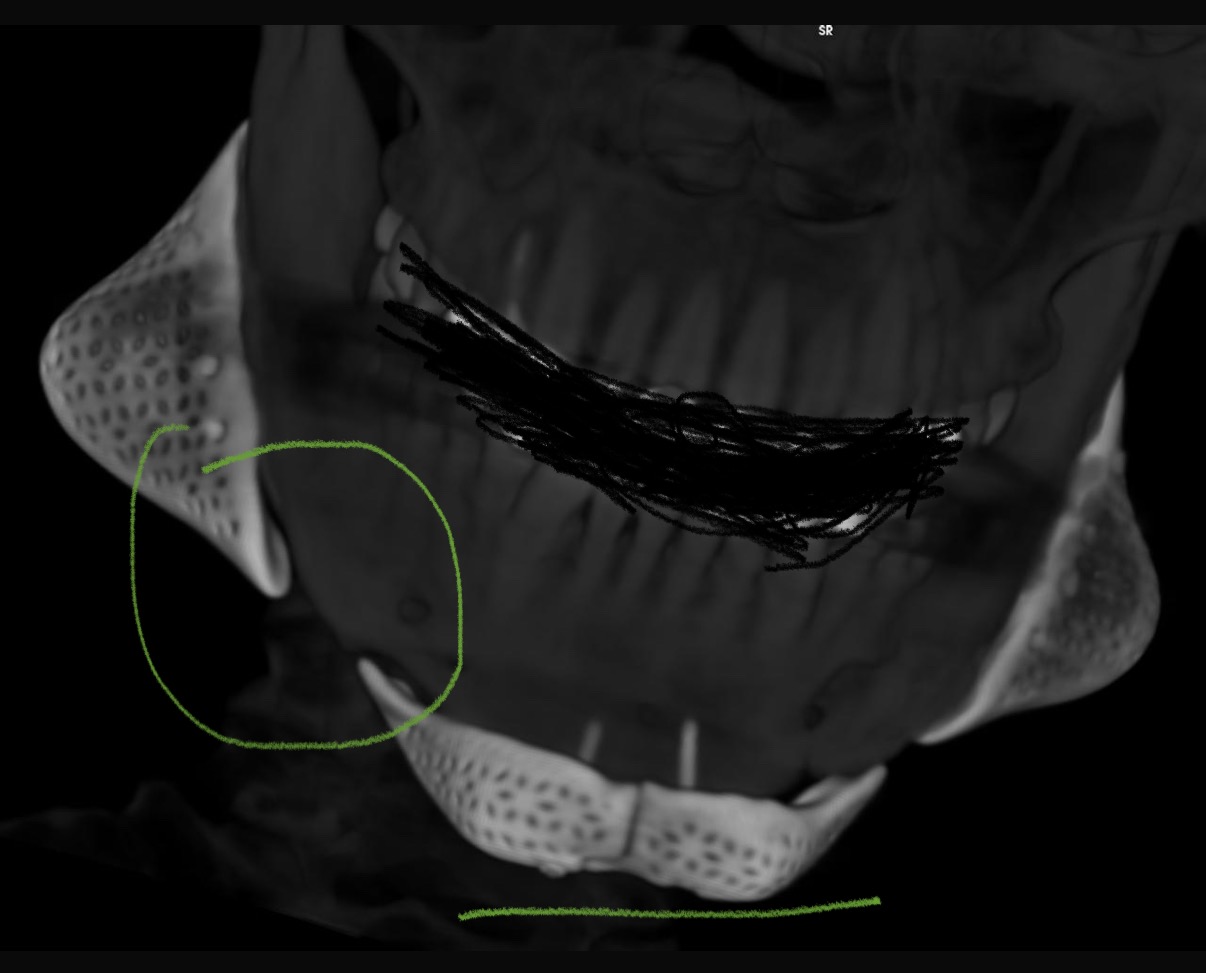

attached you will see my scans taken soon after surgery. wonky chin, off centre, right jaw not positioned the same as left. right jaw and chin flaps not even on the bone, left cheek majorly misplaced and supraorbitals extremely low. they may seem normal under the Ct scan but in real life the issues are magnified.

Also they also look like they were installed by a child. look at this one, look at dem gaps

Also they also look like they were installed by a child. look at this one, look at dem gaps